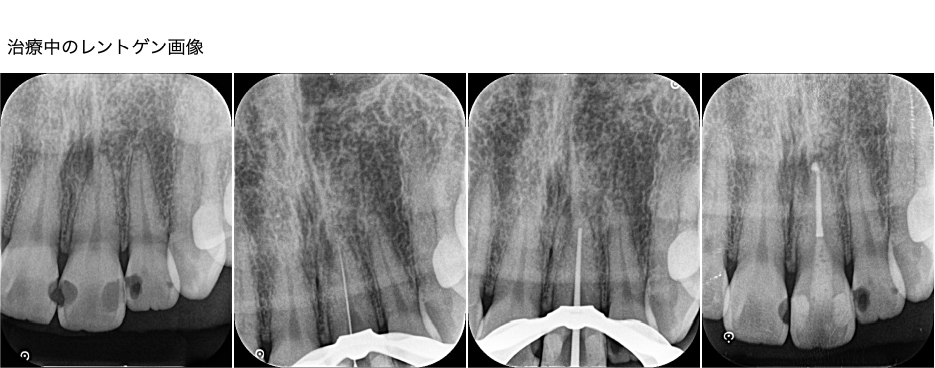

歯科治療で使用する歯ぐきに対する通常の麻酔(局所麻酔)も、眠ったことを確認してから行います。麻酔後、まずは古い詰め物と虫歯を取り除き、レジンで虫歯だった部分を修復しました。その後、ラバーダムを装着し、根管治療を開始しました。1根管のみの比較的シンプルなケースであったため、ラバーダム装着後、45分程度で治療は終了しました。